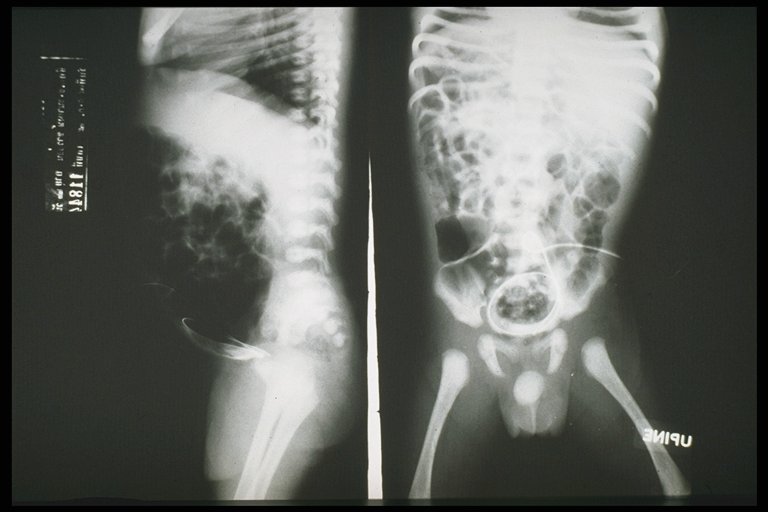

Plain X-ray shows the catheter inside the peritoneal cavity

Contrast filled through the catheter into the intestine - patent vitelline duct

Fistulogram demonstrated the tract connected between the umbilicus and the intestine